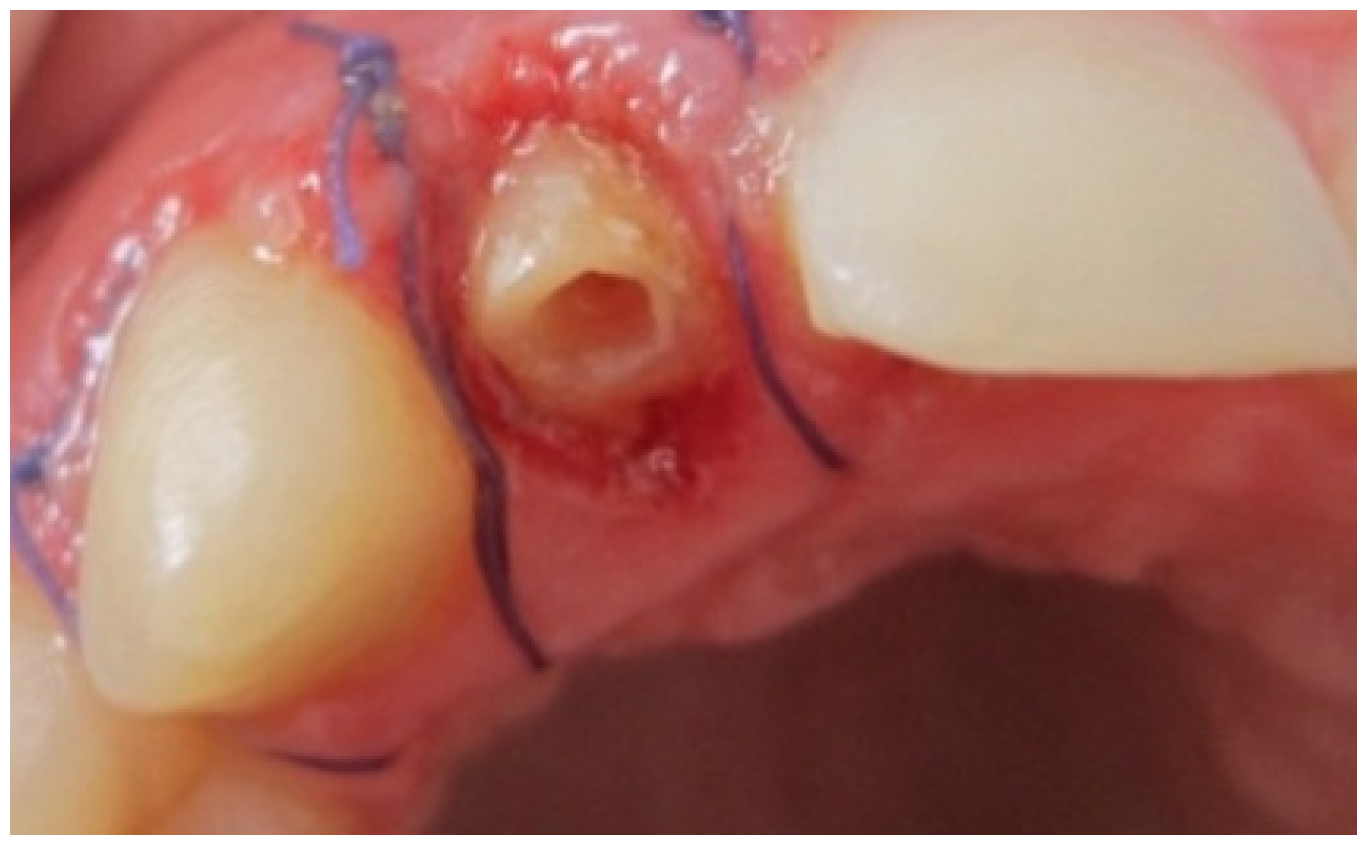

A 25-year-old dental student presented to the department of prosthetic dentistry with a chief complaint of poor aesthetics due to her imperfect metal ceramic single crown in the lateral incisor. She was bothered about the visible dark areas under the crown margins and requested an aesthetic rehabilitation. She also expressed her dissatisfaction with its color and shape. Intra oral examination showed dark gingival margins in the lateral incisor caused by metal frame (Figure 1). Soft tissues were evaluated as healthy with a wide band of attached gingiva in the maxillary region and a good oral hygiene.Visual assessment and Periodontal probing revealed a thick healthy gingival biotype with gingival thickness of 2 mm. and a sulcus depth of 2 mm. Bone sounding revealed a crest position in close relationship relative to anticipated post-surgical gingival margin level (2.5 mm). As the patient presents a thick periodontal biotype, this would significantly influence the post-operative procedure in favor of the esthetically desired outcome as this type is less prone to post-surgical recession.

Figure 1. Intra oral view showing the grayish shadow caused by the metal based crown.

Sutures were finally advocated after reapplication of the gingiva to provide a healing less exposing the operation site to the oral environment (Figure 4) [18].

Figure 4. Crown lengthening.